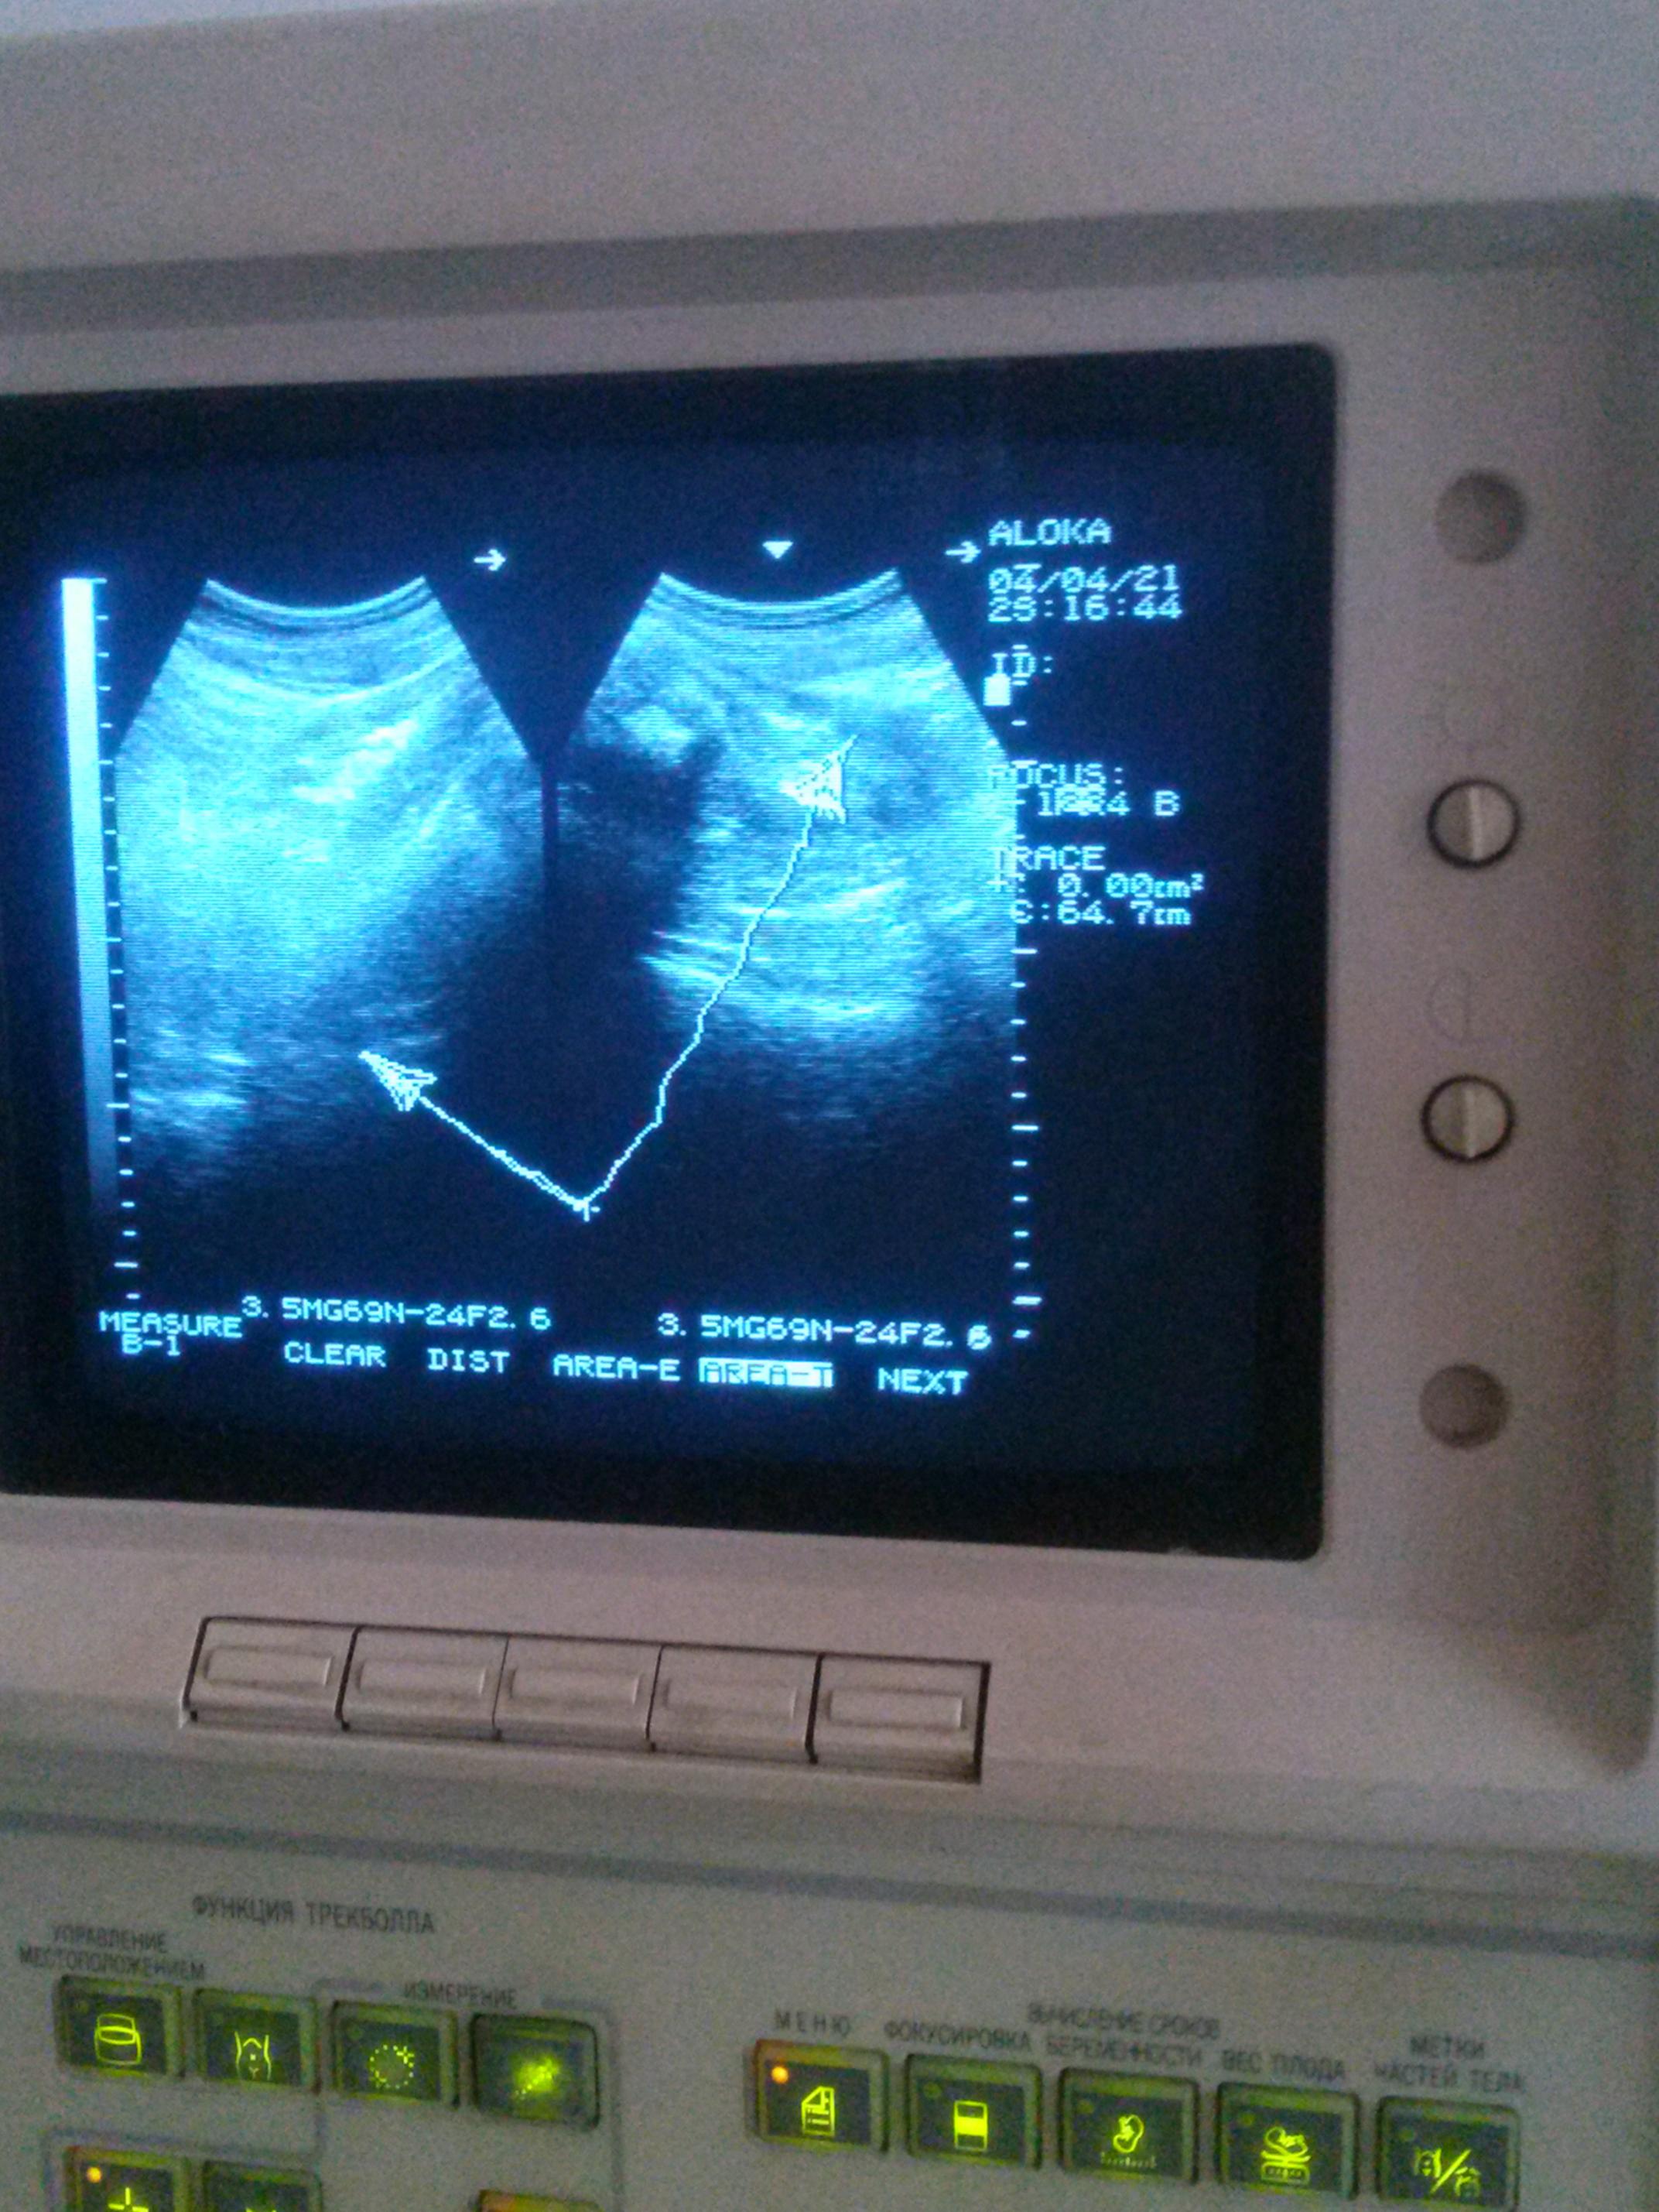

И вот почти год назад у меня обнаружились язва и рак желудка. Не верил, что это у меня может случиться - бросил курить, как ушел с армии, пили очищенную воду...

Хороший результаты - метастаз вроде нет, кроме нескольких пораженных лимфоузлов, неплохие общие анализы крови,

плохой - как выразился хирург-онколог - "уже далеко не первая стадия".

В национальном институте рака в центральную вену имплантировали У-порт ( 12 тыс грн), т. к. химия тяжелая, капает около 70 часов, зачастую сжигает вены на руках, а после многомесячных содовых капельниц на левой руке вены стали прятаться, правая - еще держится. Только за первый заход ушло больше 1000$.

Сейчас прошел 2 химии, надо еще 2, затем резектомия желудка, затем еще 4 химии, возможно и больше. Обещают - каждая последующая химия тяжелее и дороже.